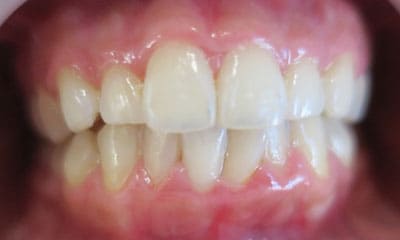

● C4を超え歯根までの虫歯を抜歯、スペースを利用して歯並び全体を整えた症例

藤沢デンタルオフィスの虫歯や破折で抜歯後の部分矯正